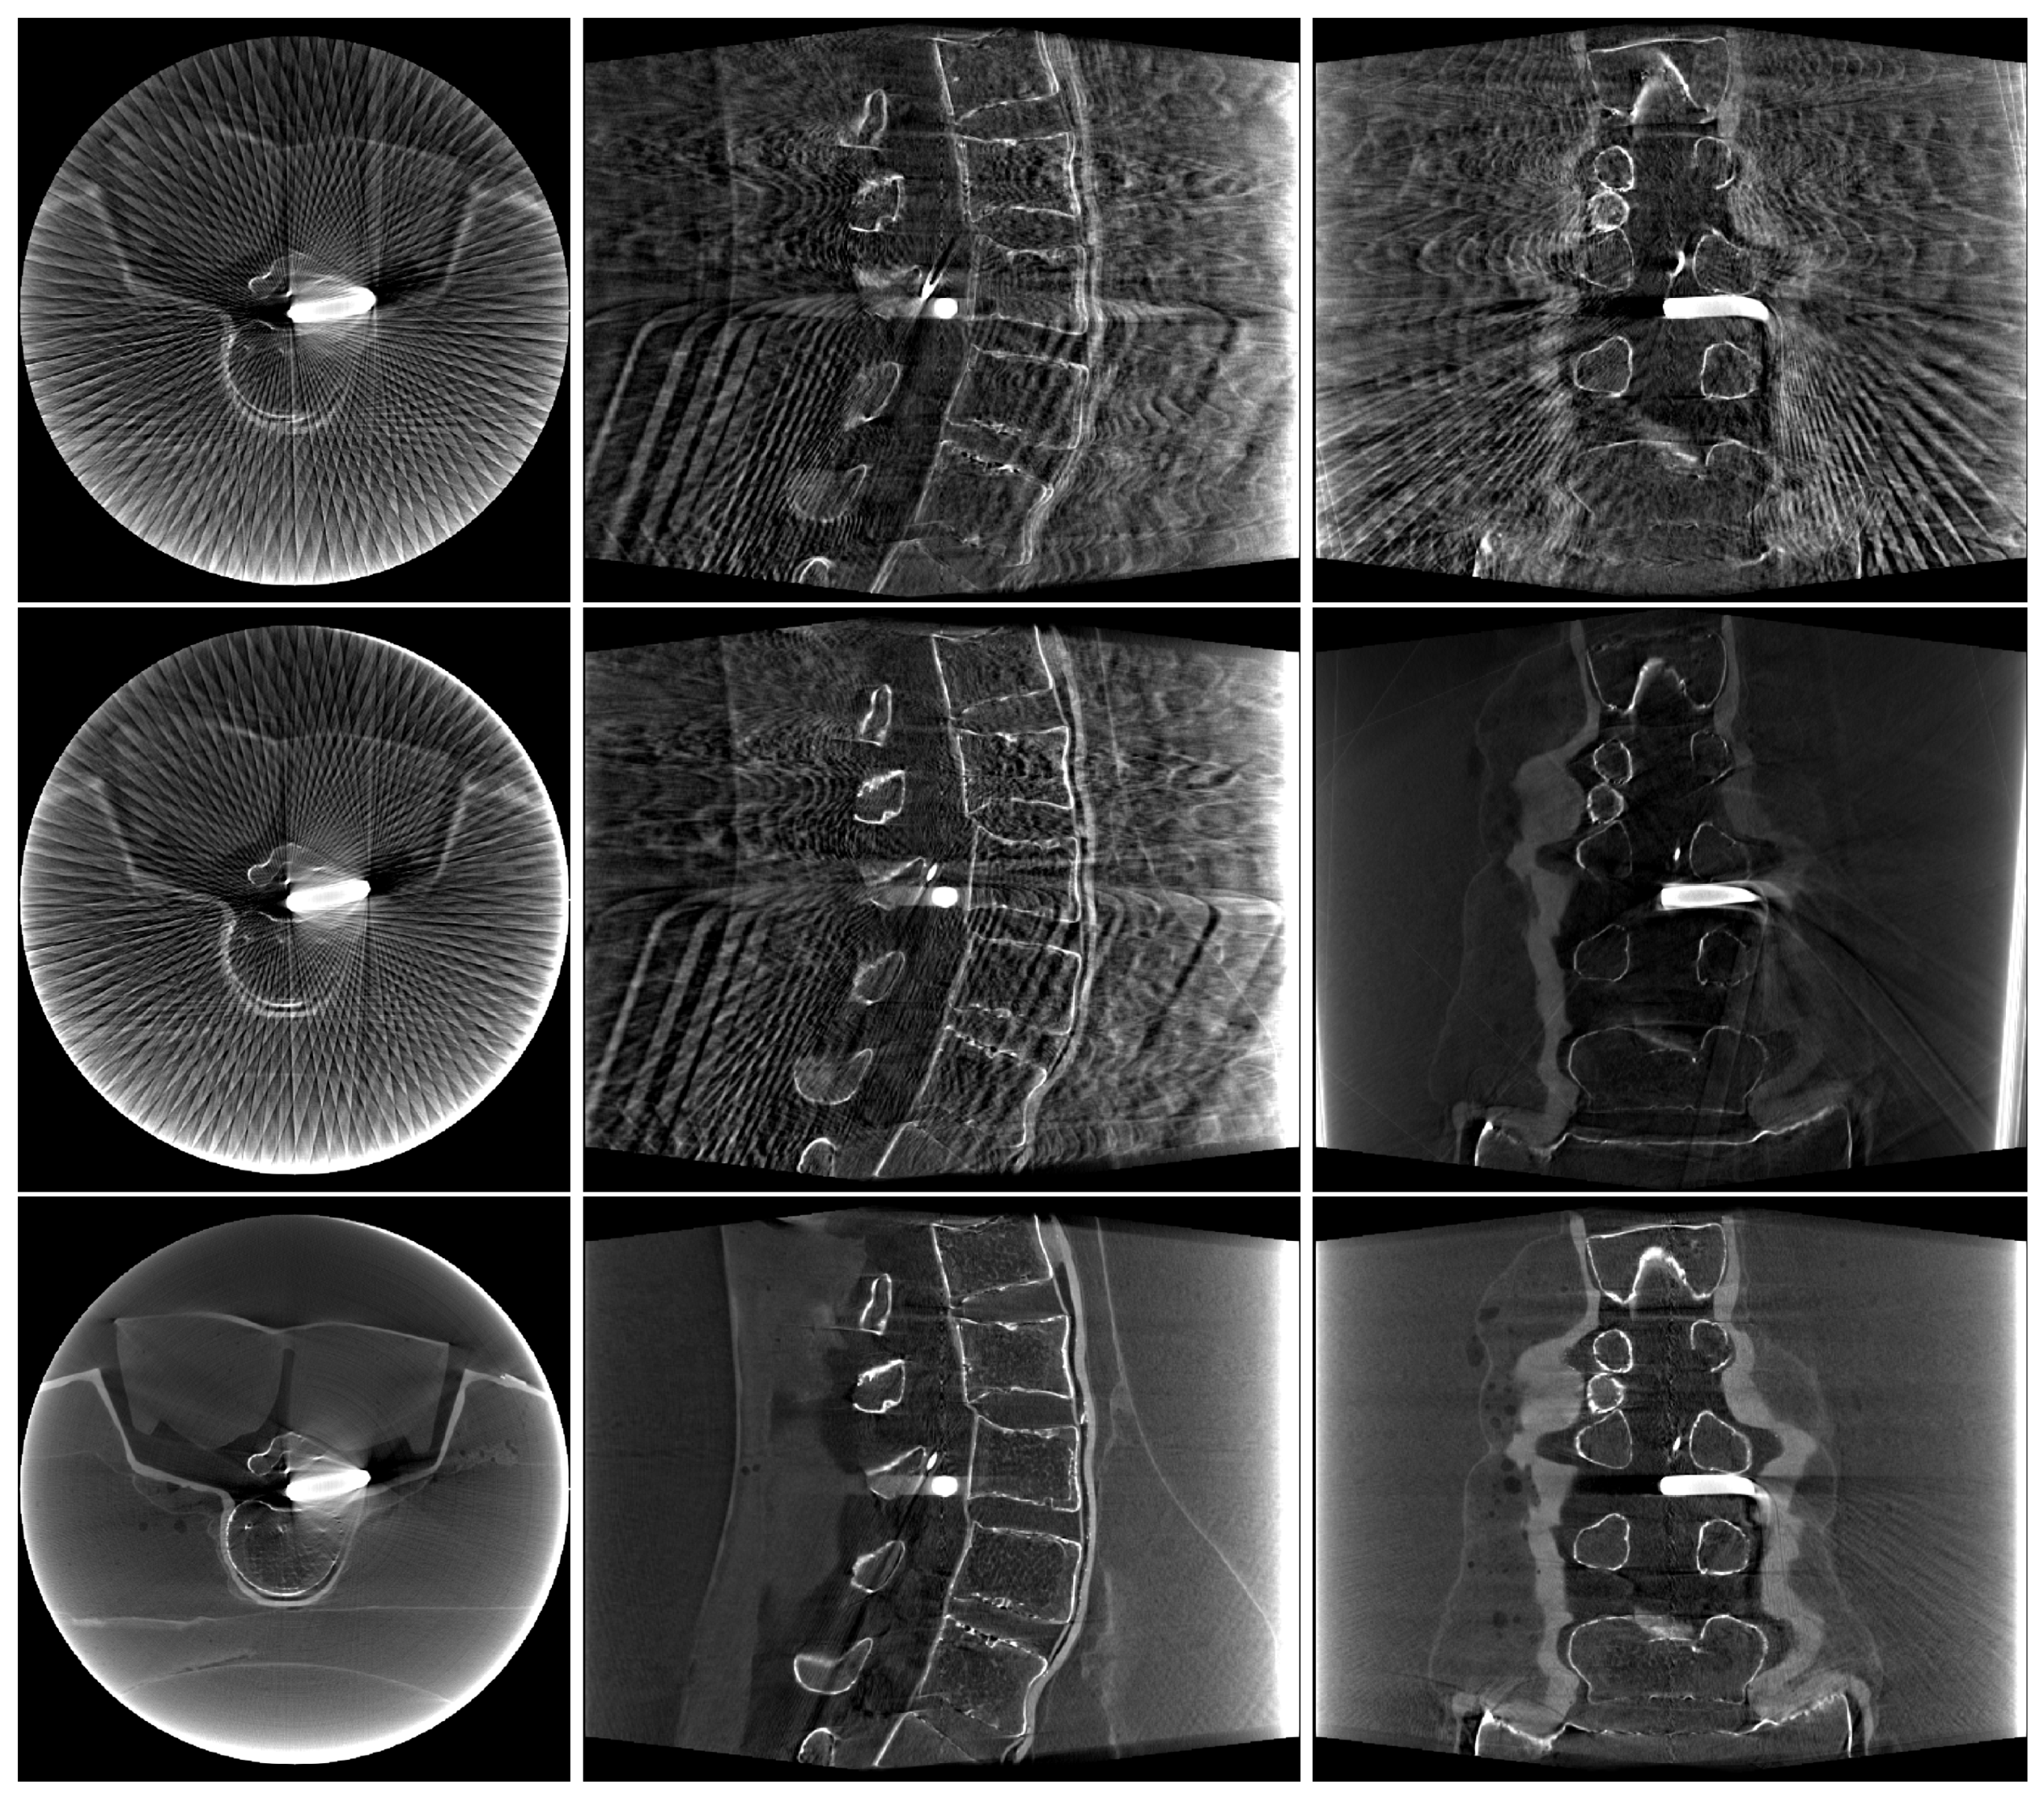

3. Results